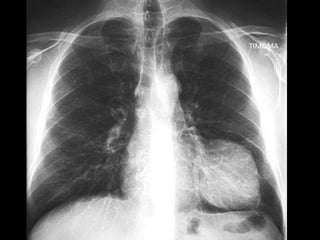

RADIOGRAFIA

• Radiografía normal

• Radiografía patológica

– Ensanchamiento mediastinal

• Técnica radiográfica

• Estructuras normales de tamaño o distribución atípica

• Estructuras vasculares

• Tumores